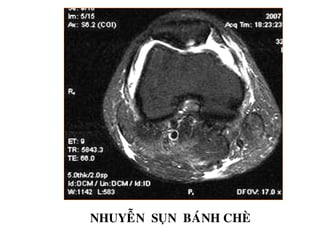

NHUYEÃN SUÏN BAÙNH CHEØ

TOÅN THÖÔNG SUÏN